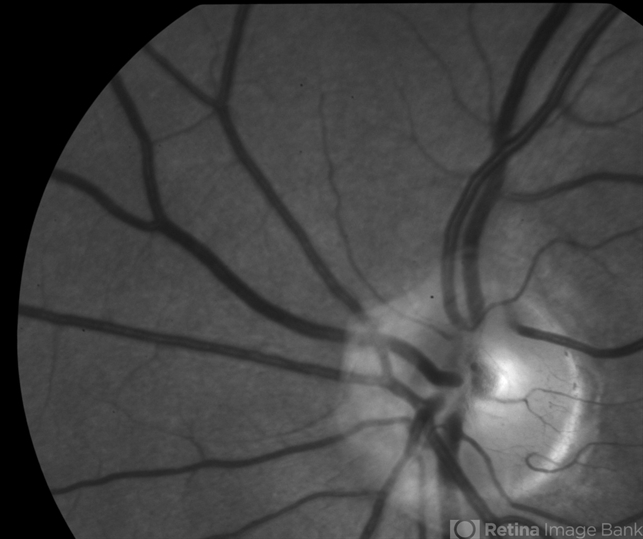

- Peripapillary Glial Proliferation

- glial proliferation, Weiss ring, posterior vitreous detachment

- 61-year-old woman with peripapillary gilal proliferation